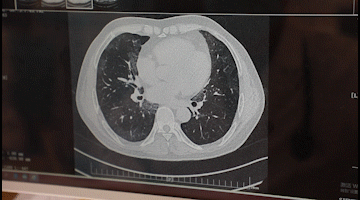

李先生入院后,胸科醫(yī)院吳昌歸院長、朱運奎副院長組織科室進(jìn)行了深入討論,為其做了詳細(xì)檢查。醫(yī)生先做了導(dǎo)航下氣管鏡冰凍活檢,但病理未獲明確診斷。根據(jù)胸部CT特征、病變過程治療的反應(yīng),醫(yī)生懷疑是罕見的肺泡蛋白沉積癥。再經(jīng)肺泡灌洗液分析、PAS染色及診斷性分段灌洗后復(fù)查,證明醫(yī)生診斷正確。李先生確診為“肺泡蛋白沉積癥(繼發(fā)性)、肺炎、1型呼吸衰竭,并伴有慢性乙肝、高血脂癥等。

經(jīng)過4次的治療,李先生沉著于肺泡內(nèi)蛋白樣物質(zhì)漸漸消失,灌洗液為透明色。復(fù)查胸部CT肺部病變明顯吸收。經(jīng)再次灌洗治療后病變完全吸收,恢復(fù)健康。